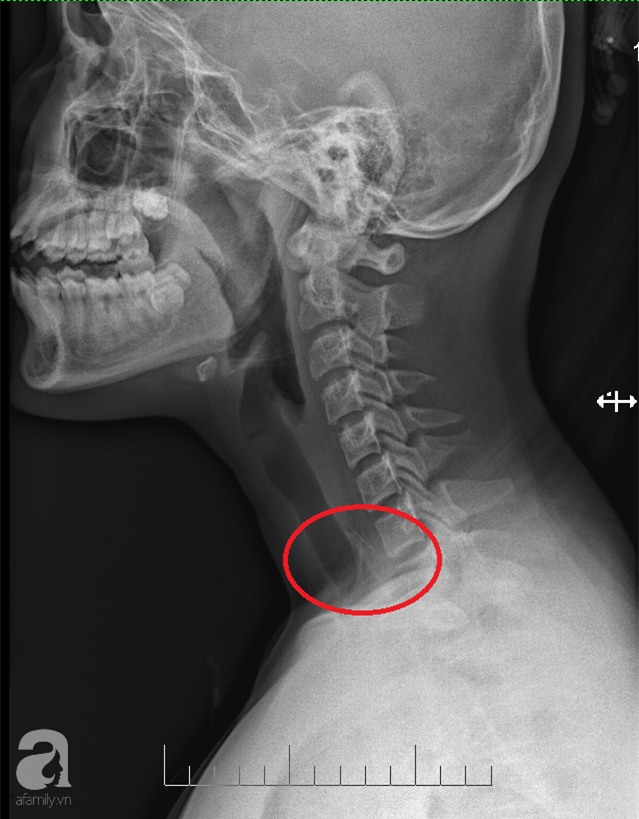

Bệnh nhi nhập viện tại Bệnh viện (BV) Hoàn Mỹ Vạn Phúc 1 trong tình trạng nuốt vướng, đau nhiều vùng hạ họng. Tiến hành thăm khám, chụp X-quang, các bác sĩ phát hiện dị vật tại thực quản đoạn ngang đốt sống cổ C2. Sau khi hội chẩn, ekip điều trị đã tiến hành cho bệnh nhân nội soi thực quản an thần để gắp dị vật.